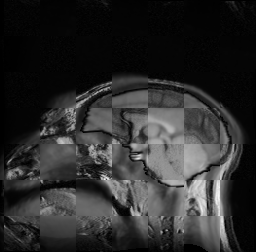

For each of the 10 subjects, we show checkerboard slices in each direction (1) before registration, first row; (2) after rigid->scaleversor->affine registration, second row; and (3) after BSpline registration, third row.

Louis